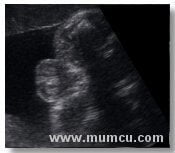

8 haftalık gebelikte amniyon kesesi, yolk kesesi ve embryo

Vajinal ultrasonografi